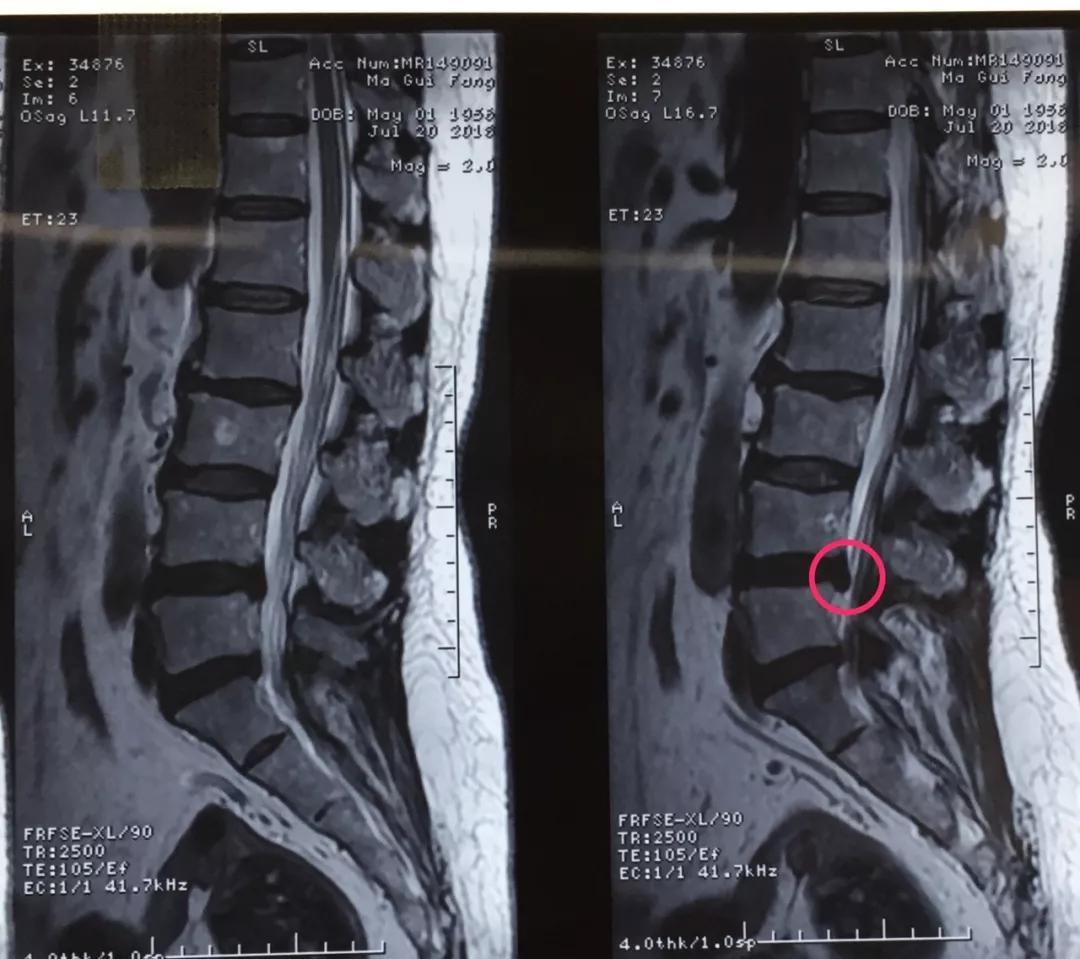

60岁的人生状态应该是退休在家,带着孙子孙女享受天伦之乐,而同样是60岁的马老太,被腰椎间盘突出症困扰了多年,稍微劳累就腰背酸痛,近几个月来又开始出现左下肢的过电样抽痛,抽的腿都抬不起来,家人带着马老太到21点游戏规则 做了检查说是腰椎间盘突出症,问了几家21点游戏规则 都说要来开刀手术,卧床两月,这下把马老太吓住了,一边是病痛折磨,一边是对手术的恐惧,正绝望之际,邻居建议马老太到21点玩法研究所 郭华副院长的专家门诊看一下,马老太并没有抱太大希望,那么多21点游戏规则 都说要手术,估计治疗方案是一样的,手术是免不了了。到中心21点游戏规则 后,郭华副院长仔细地询问了马老太的病史,并进行了细致的查体,然后看了看片子,对马老太说:“你这个情况确实是腰椎间盘突出症,但是不需要全麻开大刀,局麻下1cm小口把椎间盘取出来就可以了,术后就可以直接下地走路了,而且你现在检查齐全了,当天住院、当天手术、当天出院,我们叫做——椎间孔镜日间手术”,马老太半信半疑的回家考虑了几天,最终马老太还是相信中心21点游戏规则 的实力,24日马老太入住骨一科后,郭华副院长、严少荣主任、姬钢主任医师中午共同为马老太局麻下实施了经皮椎间孔镜下髓核摘除术,手术共计一小时,手术完马老太抬腿就不痛了,郭华副院长告诉马老太,你这个情况完全可以出院走路回家了,可把马老太高兴坏了。

郭华副院长介绍:随着人口老龄化,腰椎间盘突出症的发病数量越来越多,而医学的进步也同样日新月异,传统的开大刀手术越来越少,我院开展的经皮椎间孔镜下髓核摘除术(PELD)是近几年来成熟起来地一种微创手术方式,局麻下不到一小时就可以取出压迫神经根的椎间盘,术后即刻解除疼痛下地走路,甚至可以做到日间手术(当日住院、当日手术、当日出院),医保报销后花费少,效果立竿见影,得到了广大患者的认可和好评。希望医学德进步给广大病患带来福音,希望我院的新技术能为更多的病人解除病痛。